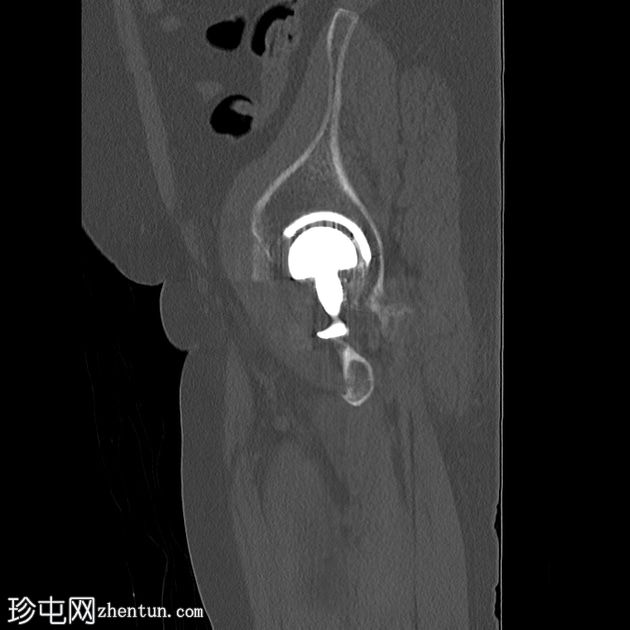

CT

轴位片

平扫

左侧全髋关节置换术。大转子基底部可见轻微移位的假体周围骨折。

大转子滑囊积液,可见脂肪-液体平面。